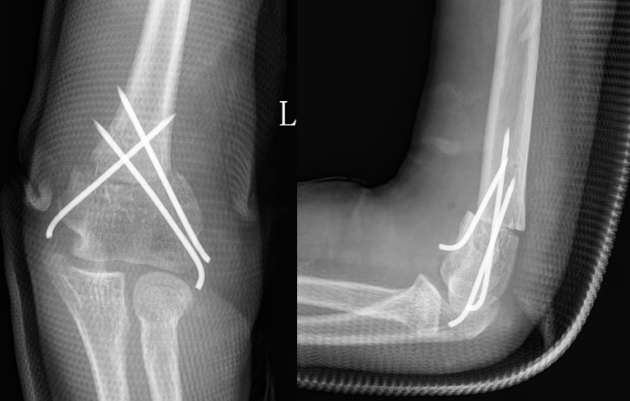

术后X线片示肘内翻矫正满意

术后X线片

取完钢针后随访